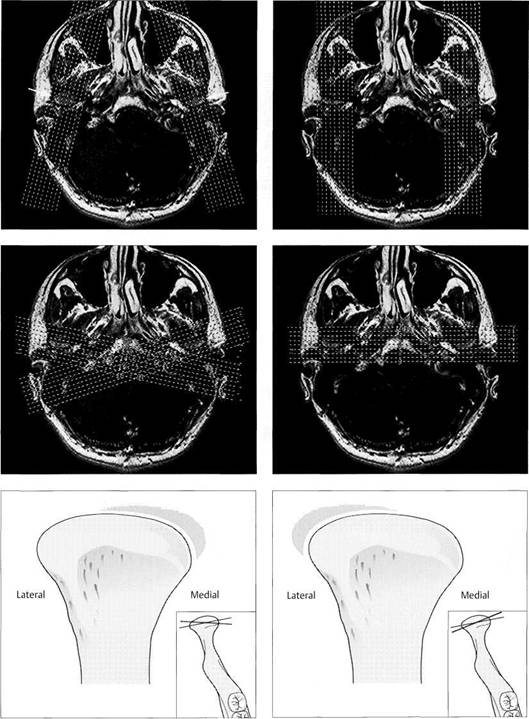

Slice alignment for sagittal images

For an MRI examination of the tem­poromandibular joint the first step is to make a horizontal orientation slice. In this plane the exact angula­tion of the condyles (arrows) can be determined. Basically, the sagittal slices can be made angled (left) or parallel with the median plane (right). Paramedian slices exhibit fewer of the artifacts caused by metal restorations in the dental arch. Furthermore, open-jaw and closed-jaw images will show the same parts of the joint in the same slice.

418 Slice orientation for frontal images

Frequently the radiologist will chose a frontal plane (right) to cap­ture images of both joints at the same time and thereby simplify the MRI examination. However, this can result in significant errors in evalu­ating the disk-condyle relation be­cause of the angulation of the condyles. Therefore, it is essential that each frontal slice be oriented parallel with the long axis of one of the condyles. This requires a sepa­rate examination for each joint.

Results of incorrect slice alignment in the frontal projection (right joint)

In the inserts the long axis of the condyle is indicated by the black line.

Left: Too much of a posterior angu­lation in the lateral region (red line) will make it appear that there is a medial disk displacement even when the disk-condyle relationship is normal.

Right: Excessive posterior angula­tion in the medial part of a normal joint will cause the MRI to mimic a lateral displacement of the disk.

For an examination of the temporomandibular joint the practitioner does not need all the MRI slices that have been prepared and stored in the computer. Three layers-a lateral, central, and medial-for each mandibular position are com­pletely adequate. One should be able to make an unequivo­cal evaluation of the fossa, disk, and condyle on each slice. In addition to the Tl-weighted scan in habitual occlusion and the T2-weighted scan at maximum jaw opening, a Tl-weighted scan in the prospective therapeutic mandibular position should always be made if there is a suspected disk displacement with repositioning.

In the past, the therapeutic disk position was determined through clinical measures alone (Owen 1984, Davies and Gray 1997a-c) or with the help of electronic axiography. According to recent studies (Kircos et al. 1987, Katzberg et al. 1996), joints that are free of clicking sounds do not necessarily have a normal disk position. Therefore an image of the "therapeutic" disk-condyle relation is important for planning the treatment. The importance of this procedure is directly proportional to the complexity of the definitive occlusal stabilization that will be required after disk reposi­tioning.

Habitual occlusion

MRI exposures at habitual occlusion are always made in a T1-weighting with the so-called spin-echo (SE) technique. The radiologist usually exposes six to eight slices, although images of only three layers (medial, central, and lateral) are necessary to adequately evaluate the disk-condyle relationship (Crowley et al. 1996). In a medial slice the lateral pterygoid muscle (arrows) can be identified. In the central slice (cen­ter) the posterior border of the as­cending ramus (arrows) is always visible.

Maximal jaw opening

The second obligatory joint series is made at maximal jaw opening in T2-weighting. The T2-weighting is well suited to reveal inflammatory reactions and joint effusions (Larheim 1995). The combination of exposures (Tl closed and T2 open) makes it possible to avoid a complete MRI series with both weightings. Again, a lateral, cen­tral, and medial slice are made. If the maximal jaw opening is not se­cure, false positive findings are like­ly to be made (Watt-Smith et al.

Therapeutic occlusion

The most important sequence of the MRI examination is the depic­tion of the positional relationships of the fossa, disk, and condyle in the treatment position of the mandible. The prognosis of a con­servative repositioning treatment depends to a large extent upon this view. To demonstrate a complete repositioning, medial, central, and lateral slices must again be made. When there is disk displacement without repositioning, this view is not as suitable as one in an angled coronal plane.